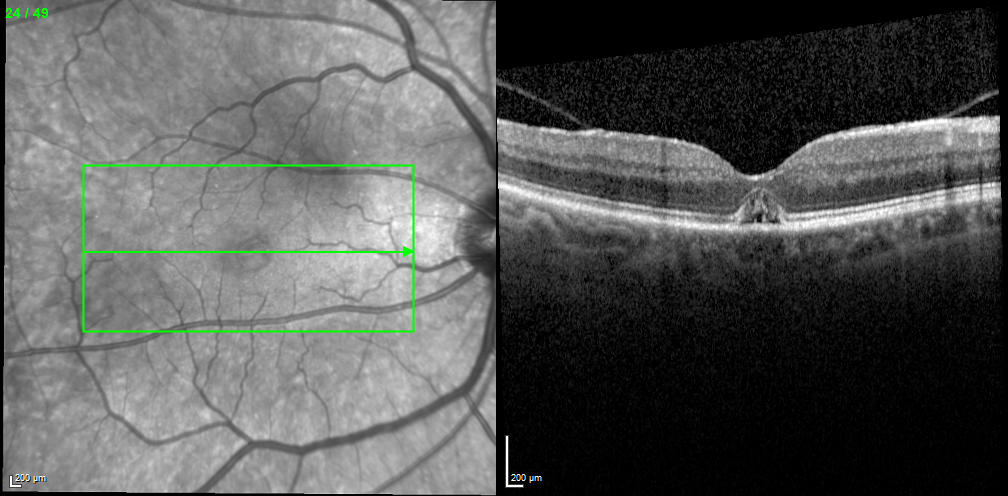

Figure 4. High-density OCT scan through the fovea 4 months after starting treatment showing a closed MH with a slightly smaller subfoveal fluid pocket.

Over the next 4 months, the drops were gradually tapered. At the patient’s last visit, at which point he was using ketorolac once daily, the MH remained closed with reduced subfoveal fluid and unchanged visual acuity or symptoms (Figure 4).